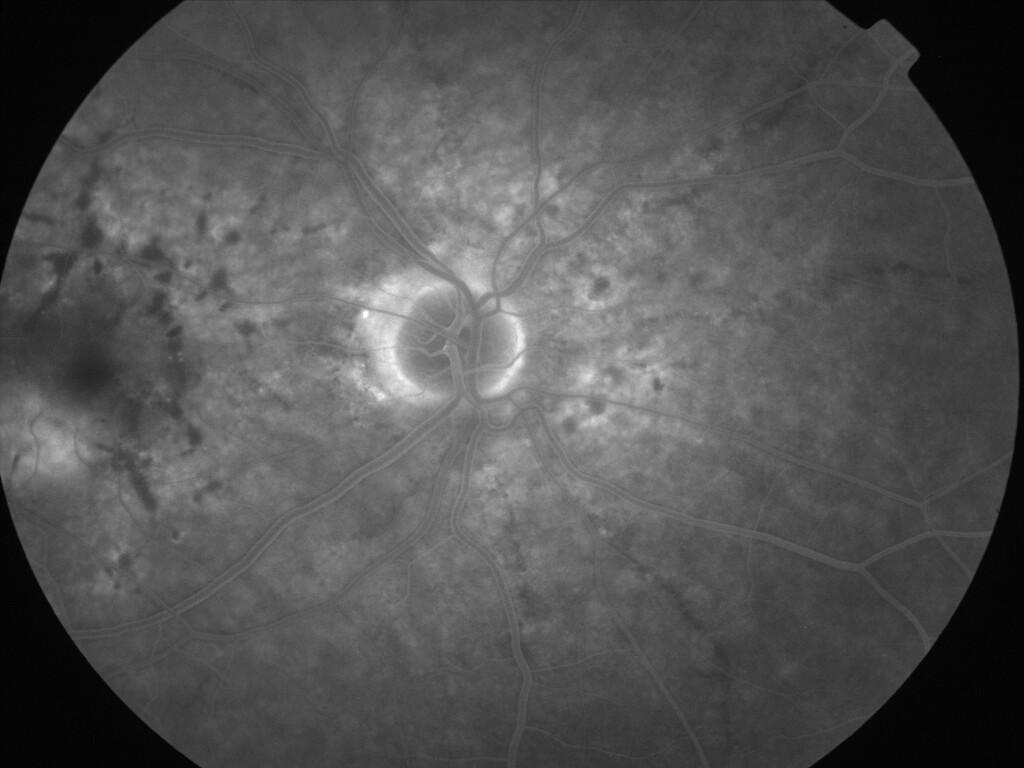

ASSOCIATION STRIES ANGIOIDES ET DYSROPHIE MACULAIRE RETICULEE

NEOVASCULARISATION